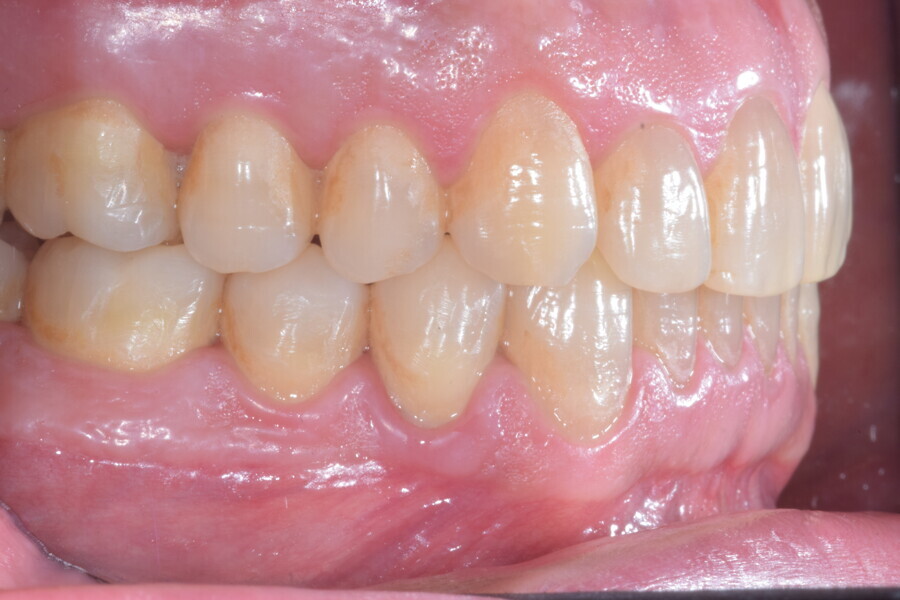

A 37-year-old male patient presented with the chief need for re establishing anterior alignment in both arches. Facial analysis showed a short face with a flat profile but proper chin projection (Figs. 9–12), and clinical examination revealed a skeletal Class I (ANB = 0.89°) and dental Class I malocclusion with severe deep bite (almost 100%), a deep curve of Spee, normal maxillary central incisor torque (Ui–FH = 110°), mild maxillary crowding and moderate mandibular crowding (Figs. 13–18). The deep bite components were represented in this patient by the severe skeletal condition of hypo divergent pattern (FMA = 14.24°) with normal maxillary and mandibular incisor inclination and decreased gonial angle (110.46°). Analysis of the cephalometric radiograph indicated a reduced lower anterior facial height, combined with a hypo-divergent pattern (Fig. 19). The only treatment option suggested was orthodontic treatment with aligners for deep bite correction with all the features described (bite ramps, pressure area, 3D curve of Spee levelling, Class II elastics and heavy occlusal contacts).

The digital treatment plan (ClinCheck) provided 12 aligners for the maxillary arch and 17 for the mandibular arch. The treatment objectives were focused on coupled vertical movements of posterior extrusion and anterior intrusion by means of bite ramps, providing for posterior disocclusion and anterior intrusion of mandibular teeth by means of extrusion attachments needed for mandibular arch levelling. The maxillary and mandibular incisors were proclined to level the upper and lower curve of Spee and to support the flat profile and the lips. Class II elastics were planned to support mandibular proclination and heavy posterior occlusal contacts with relative posterior extrusion. Lateral and posterior maxillary torque were planned to be close to 0°, to achieve wider arch design and ideal intercuspation. No digital over-engineering was planned in the set-up. Because of the age of the patient, the aligners were changed every ten days for a treatment time of less than six months. At the end of the first stage of aligners (Figs. 20–24), an additional stage was planned to improve molar intercuspation without elastics with a digital plan of five further aligners. This brought the total treatment time to 7.5 months since the additional aligners were changed every week.

At the end of the treatment, Class I canine and molar relationships were obtained, maxillary incisor inclination was slightly increased (Ui–FH = 112°), mandibular incisor inclination (IMPA = 97.09°) was fully corrected by means of proclination and the divergency was slightly increased (SN–GoGn = 27°) because of the relative posterior extrusion and use of Class II elastics—a small variation (1°), which is interesting considering the age of the patient (Figs. 25–35). A balanced smile arc was obtained with an ideal relationship between the maxillary incisors and lower lip, and torque control of the lateral and posterior segments generated a broader smile.